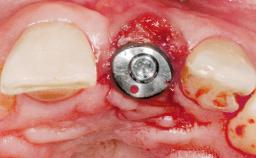

Immediate Flapless Placement of an Implant in a Maxillary Left Central Incisor Site

A 42-year-old female patient was referred to our clinic at the School of Dentistry of the University of São Paulo in November 2004, presenting a deficient restoration in the upper left central incisor. The clinical examination revealed no gingival retraction or any signs of gingival inflammation and, therefore, previous periodontal treatment was not considered. The patient presented a high lip line at full smile and a thin tissue biotype. This combination characterized a high-risk situation from an anatomic point of view, which required careful preoperative planning and cautious surgical execution.

| Placement Protocol | Immediate implant placement |

| Tooth Site | Maxillary incisor or canine |

| Socket Morphology | Single-root socket |

| Socket Integrity | Sufficient, with intact bone walls |